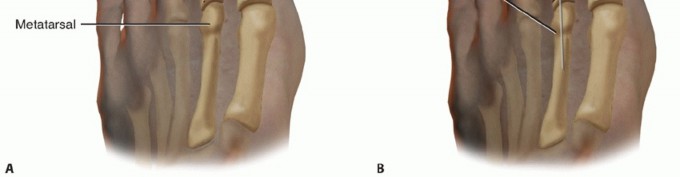

After two 4-0 stay sutures have been placed longitudinally into the tendon 4 cm proximal to the MTP joint, the tendon is transected between these two sutures (TECH FIG 3A).

TECH FIG 3 • A. Stay suture placement along the EDB tendon and transaction point identified by dashed line between the two sutures. The EDL tendon is also shown after Z-lengthening. B. Transfer of distal EDB stump plantar to transverse metatarsal ligament and lateral to second metatarsal. (continued)

Care is taken to maintain the integrity of the distal EDB tendon insertion, and the distal EDB tendon stump is then passed from distal to proximal underneath the transverse metatarsal ligament and lateral to the MTP joint (TECH FIG 3B).